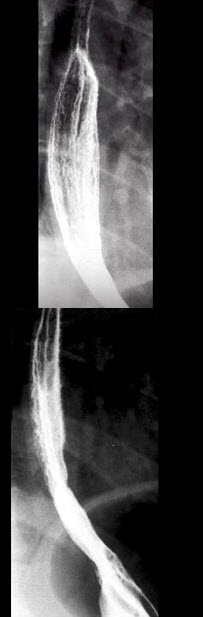

12、单项选择题

男,34岁,胸骨后烧灼痛1周,伴吞咽痛,餐后平卧时加剧,食管钡餐检查如图,最可能的诊断是()

A.食管癌

B.贲门失弛缓症

C.返流性食管炎

D.食管静脉曲胀

E.正常食管表现